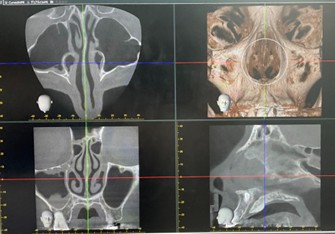

副鼻腔症状の診断

炎症や病変の広がりを正確に把握

→副鼻腔ページへ

副鼻腔画像